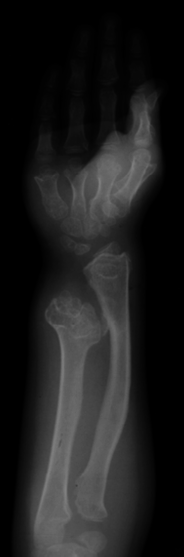

Background: The purpose is to determine the location and type of osteochondromas in patients with multiple osteochondroma of the hand as well as the presence of shortening and angulation. Second, it aims to establish longitudinal data on the change in tumors.

Methods: Retrospective review of patients with multiple osteochondroma affecting the hand evaluating the location and type of tumors as well as the presence of shortening and angulation is done. We examined radiographs from final follow-up and analyzed them based on patient age at presentation (group I = ages 2-6; II = ages 7-10; III = ages 11-19), to determine changes over time and any differences in the number of tumors, location, and shortening and angulation.

Results: The most affected bones were the index and small finger metacarpals with an increase seen around the metacarpophalangeal (MCP) joints. The most shortening and angulation were seen on the ulnar side. Group II had the most tumors and the most bones with angulation. Twenty-three hands had longitudinal follow-up with an overall increase of 2.7 tumors per hand with a range of loss of 8 to gain of 16. There was an increase in the number of bones with angulation and shortening. Group I showed the largest increase in tumors, shortening, and angulation.

Conclusions: The ulnar side and bones around the MCP joints are affected most commonly. The largest change was seen as the patients went from young childhood into adolescence, which may be due to rapid growth during this time. This is the largest study of these patients with the longest longitudinal data.